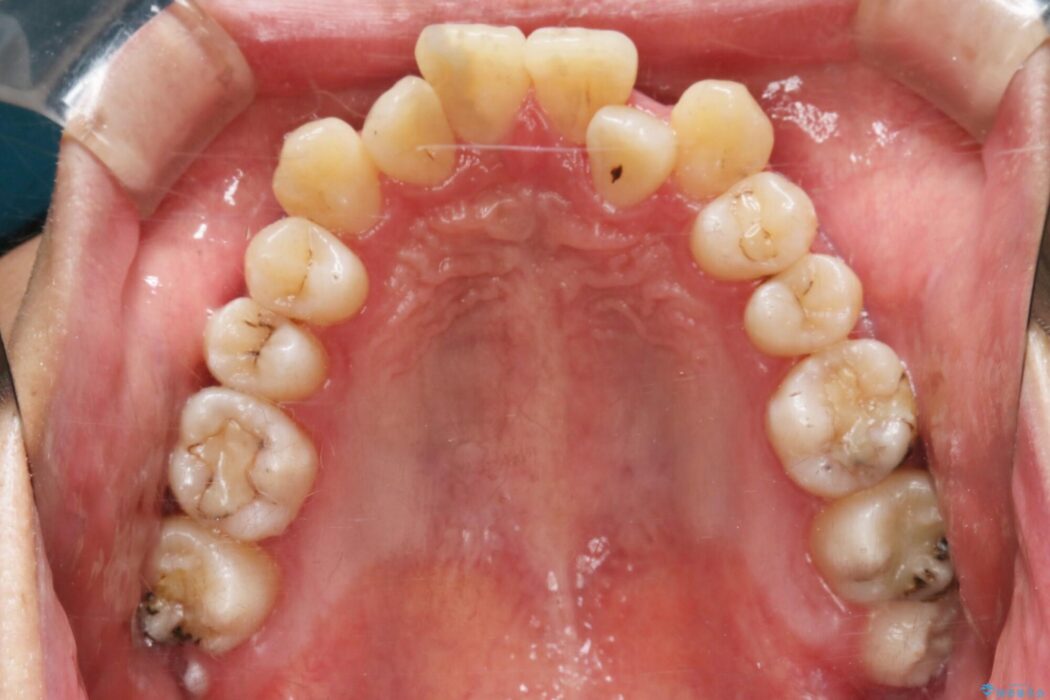

治療動機

上顎歯列弓のガタガタを治療したいとのことで来院されました。

抜歯をしない治療について

非抜歯での矯正治療ではスペースの確保が必要となります。

・歯の遠心移動

・歯列弓の拡大

・IPR(歯の側面を少し削る)

本症例では上記3つの方法を複合的に組み合わせた治療を行いました。